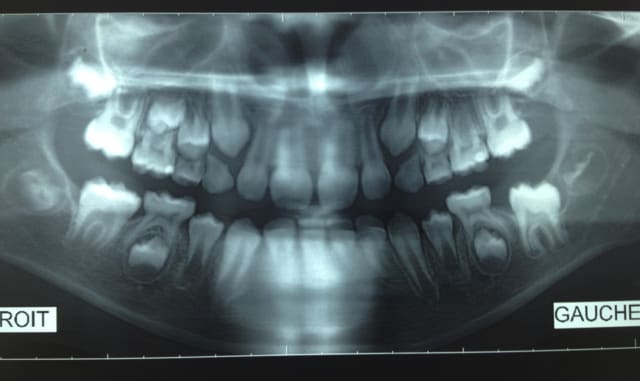

Malheureusement disparue pendant 3 ans, je l'a revoie au mois de juillet à 11 ans donc.

pas d'évolution des 36 et 46 et pas d'évolution non plus des germes de 45 et 35

Il y a quand même eu une édification radiculaire des 6 et une migration, certes elle n'est pas très importante compte tenu de la durée écoulée.

Sur les 2 panos, on voit quand même une bonne épaisseur de gencive. Une gencive fibreuse fait partie des causes de retard d'éruption même si pour les molaires c'est pas le plus fréquent.

Par contre pour 35 et 45, elles n'ont pas bougé. Vu leur édification radiculaire, il faut bien protéger 75 et 85 car à ce rythme là elle va les conserver longtemps et je ne vois pas ce qui pourrait les forcer à se presser.

Le retard pour les 7 est pas mal non plus.